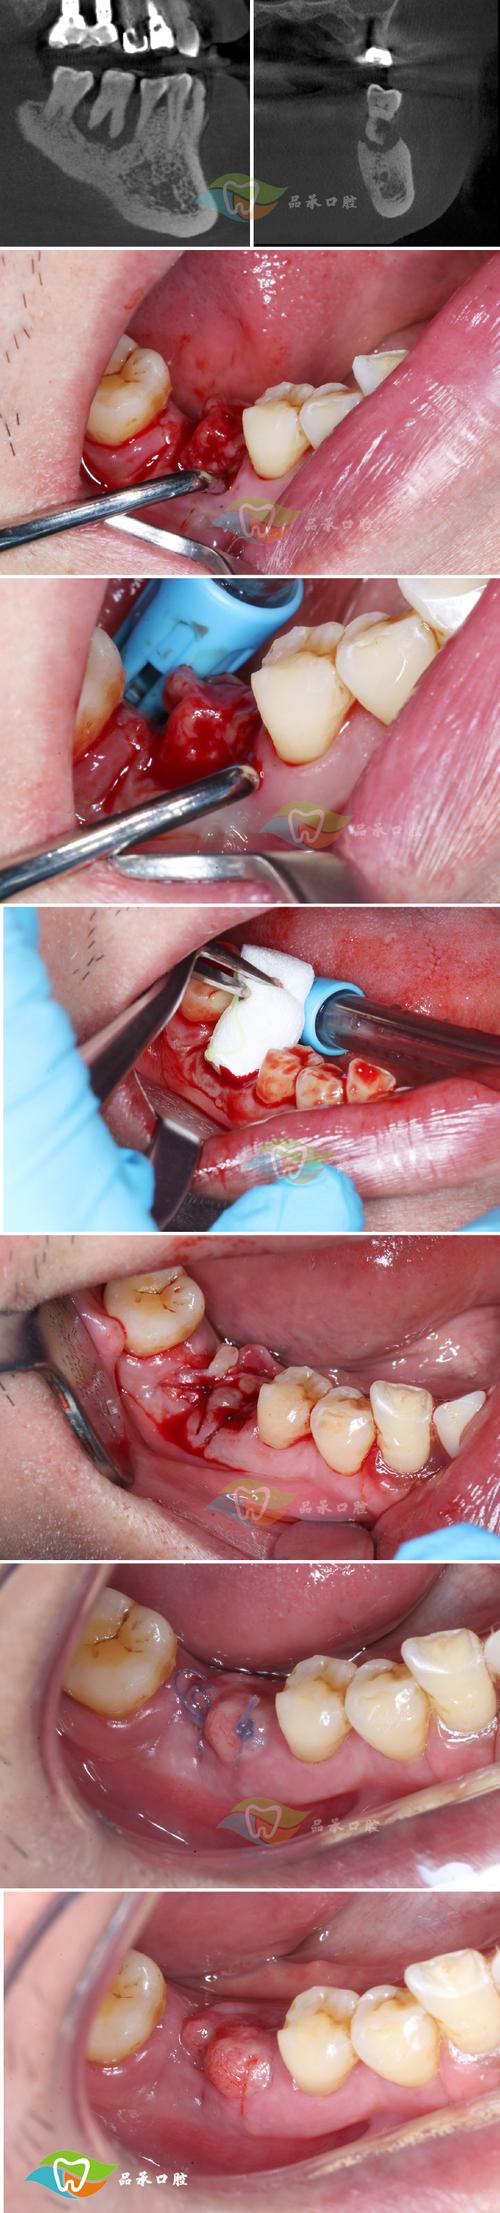

- 重度创伤(牙根吸收>1/2或牙根穿孔):需终止正畸治疗,拔除患牙,避免影响邻牙健康,后期可考虑种植义齿修复。

- CBCT:三维重建清晰显示牙根形态、吸收范围及牙槽骨骨折部位,是早期诊断和鉴别诊断的重要工具。